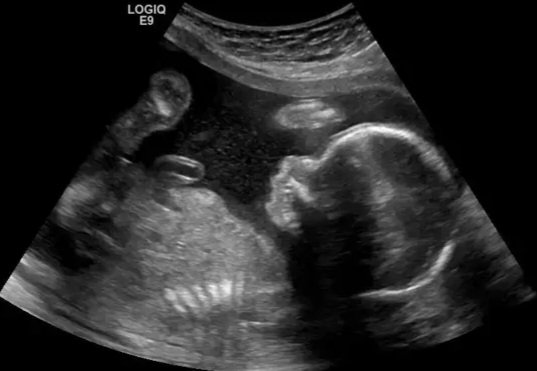

The whole Christmas story hinges on birth.

Birth is messy. Risky. Life-changing.

Spiritual birth is also messy. Risky. Life-changing.